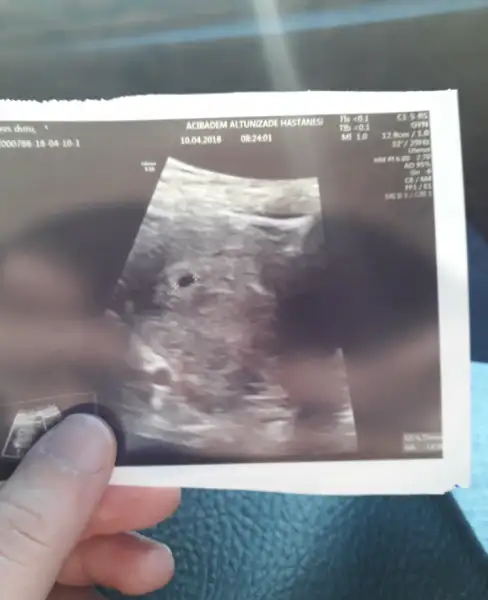

Cok sevindim canim hadi bakalim kalp atisinida duyarsiniz insallah :)Kızlar merak ettiğiniz icin çok sağolun keseyi gördük 5+5 günlü çıktı ultrasonda 10 gün sonrA kalp atışı icin çağırdı insallah kalp atışını da duymayı nasip eder rabbim

Masallah Cnm oyyy oyyy teyzesi çok sever o minnagi çok sevindim Cnm :) doktor ne dedi kalp atışı icin ne zaman çağırdı :)Herkese merhaba

Günün ilk haberi bizden gelsin teyzeleri. Şimdi doktordan eve dönüyoruz. Kesemizi gördük elhamdulillah

Sizden de bekliyorum güzel haberleri canlarım

Maşallah canım benim Allah hayırlısıyla kucağına almayı da nasip etsin kist ne alemdeHerkese merhaba